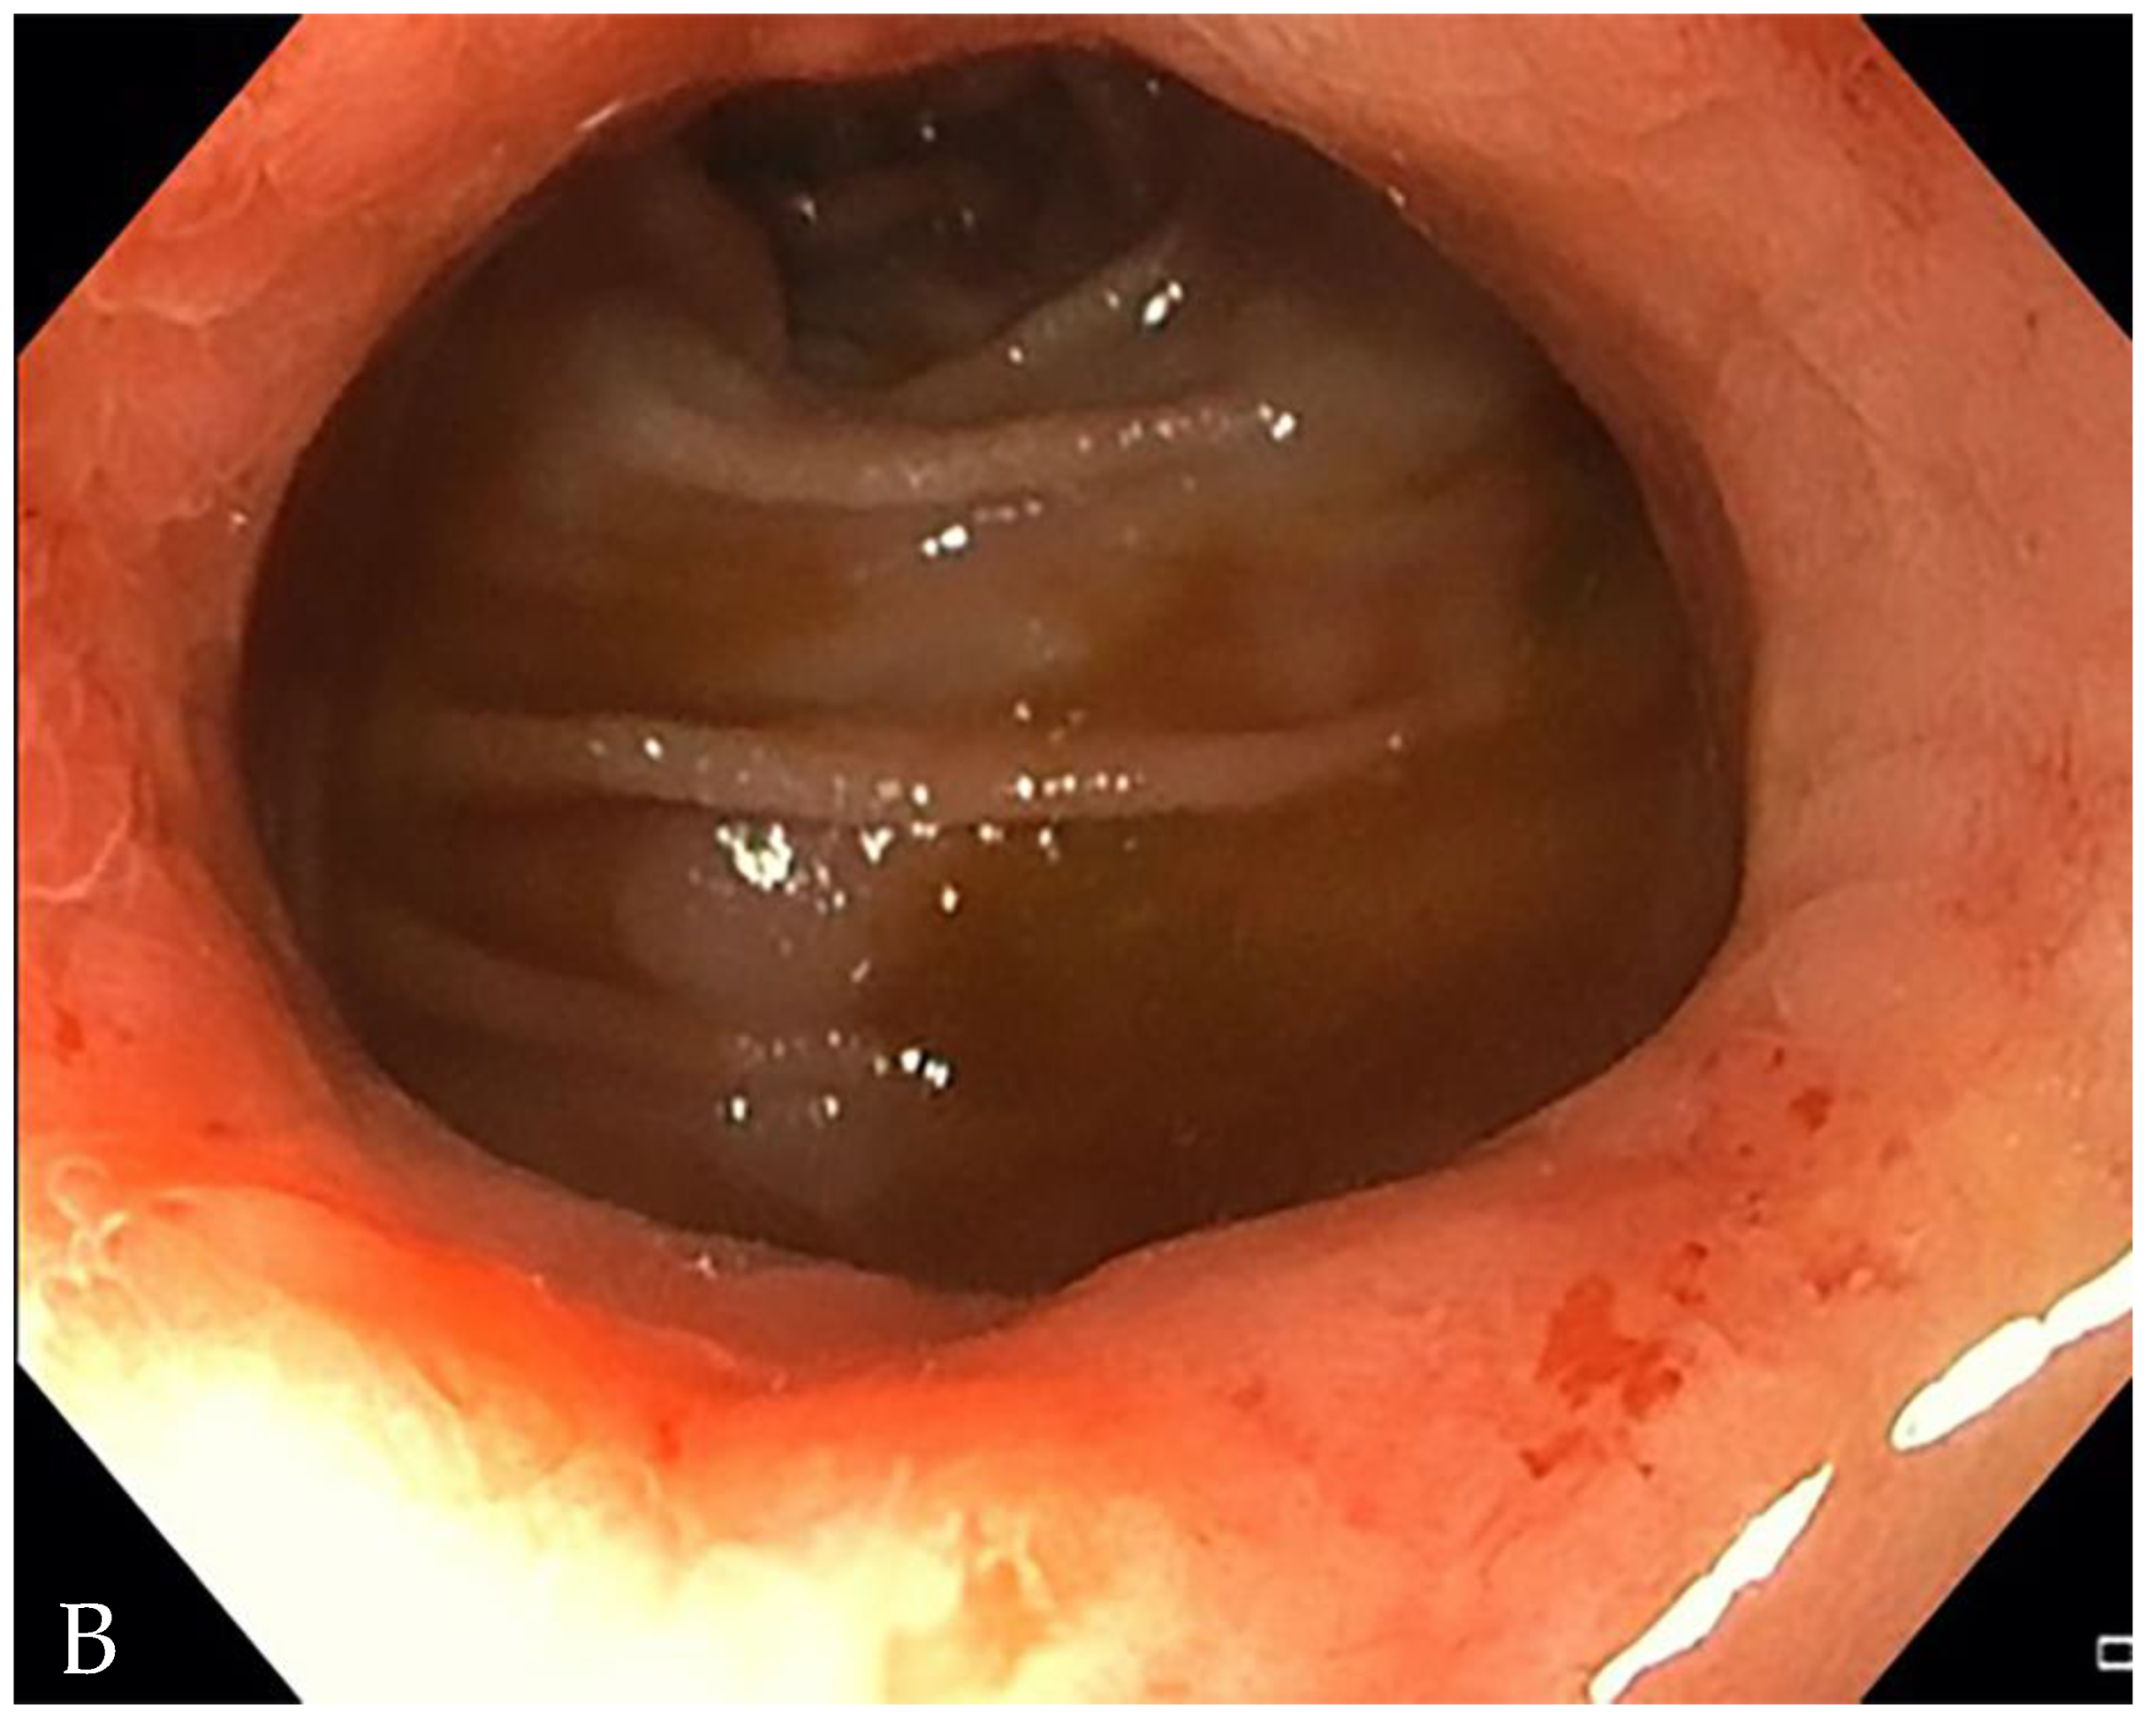

- A normal bowel loop caliber ranges between 2 and 2.5 cm. A bowel lumen is dilated when it has a maximum diameter greater than 2.5–3 cm. The dilation is mild when the upstream lumen is dilated up to 4 cm and severe when it is more than 4 cm (Figure 3) [24]. Pre-stenotic bowel dilatation should always be checked, as it is a sign related to bowel obstruction. Moderate to severe stenosis was determined via double-contrast imaging (conventional barium study) with a sufficient amount of injected air, and stenosis was defined as stenosis in which the lumen was less than one half that of neighboring healthy intestine [25].